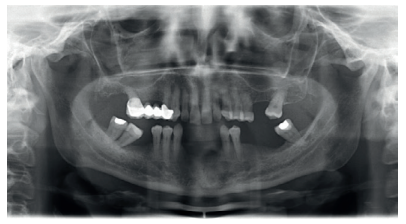

Currently in implant dentistry, we are increasingly faced with cases of extreme bone resorption that force us to implement different surgical dental implant techniques. The coexistence of vertical and horizontal atrophy makes successful resolution of these cases more difficult, as well as having to face these types of more complicated situations with increasing frequency, due to patients demanding implant treatment even in such very severe cases. It is not uncommon therefore to use combined techniques which include ridge expansion or short implants, for example. The following clinical case presented advanced horizontal and vertical alveolar atrophy in the right and left posterior regions of the mandible. The treatment plan included the use of short implants for the vertical atrophy and a two-stage alveolar ridge split to treat the horizontal atrophy.

horizontal resorption of the antero-inferior sector in the incisor

area; (A) area corresponding to tooth 42 (B) area corresponding

to tooth 32 (C) Planning of the expander implant in the CT cut.